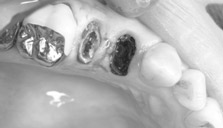

歯根も歯折していました。 |

慎重に抜歯します。 |